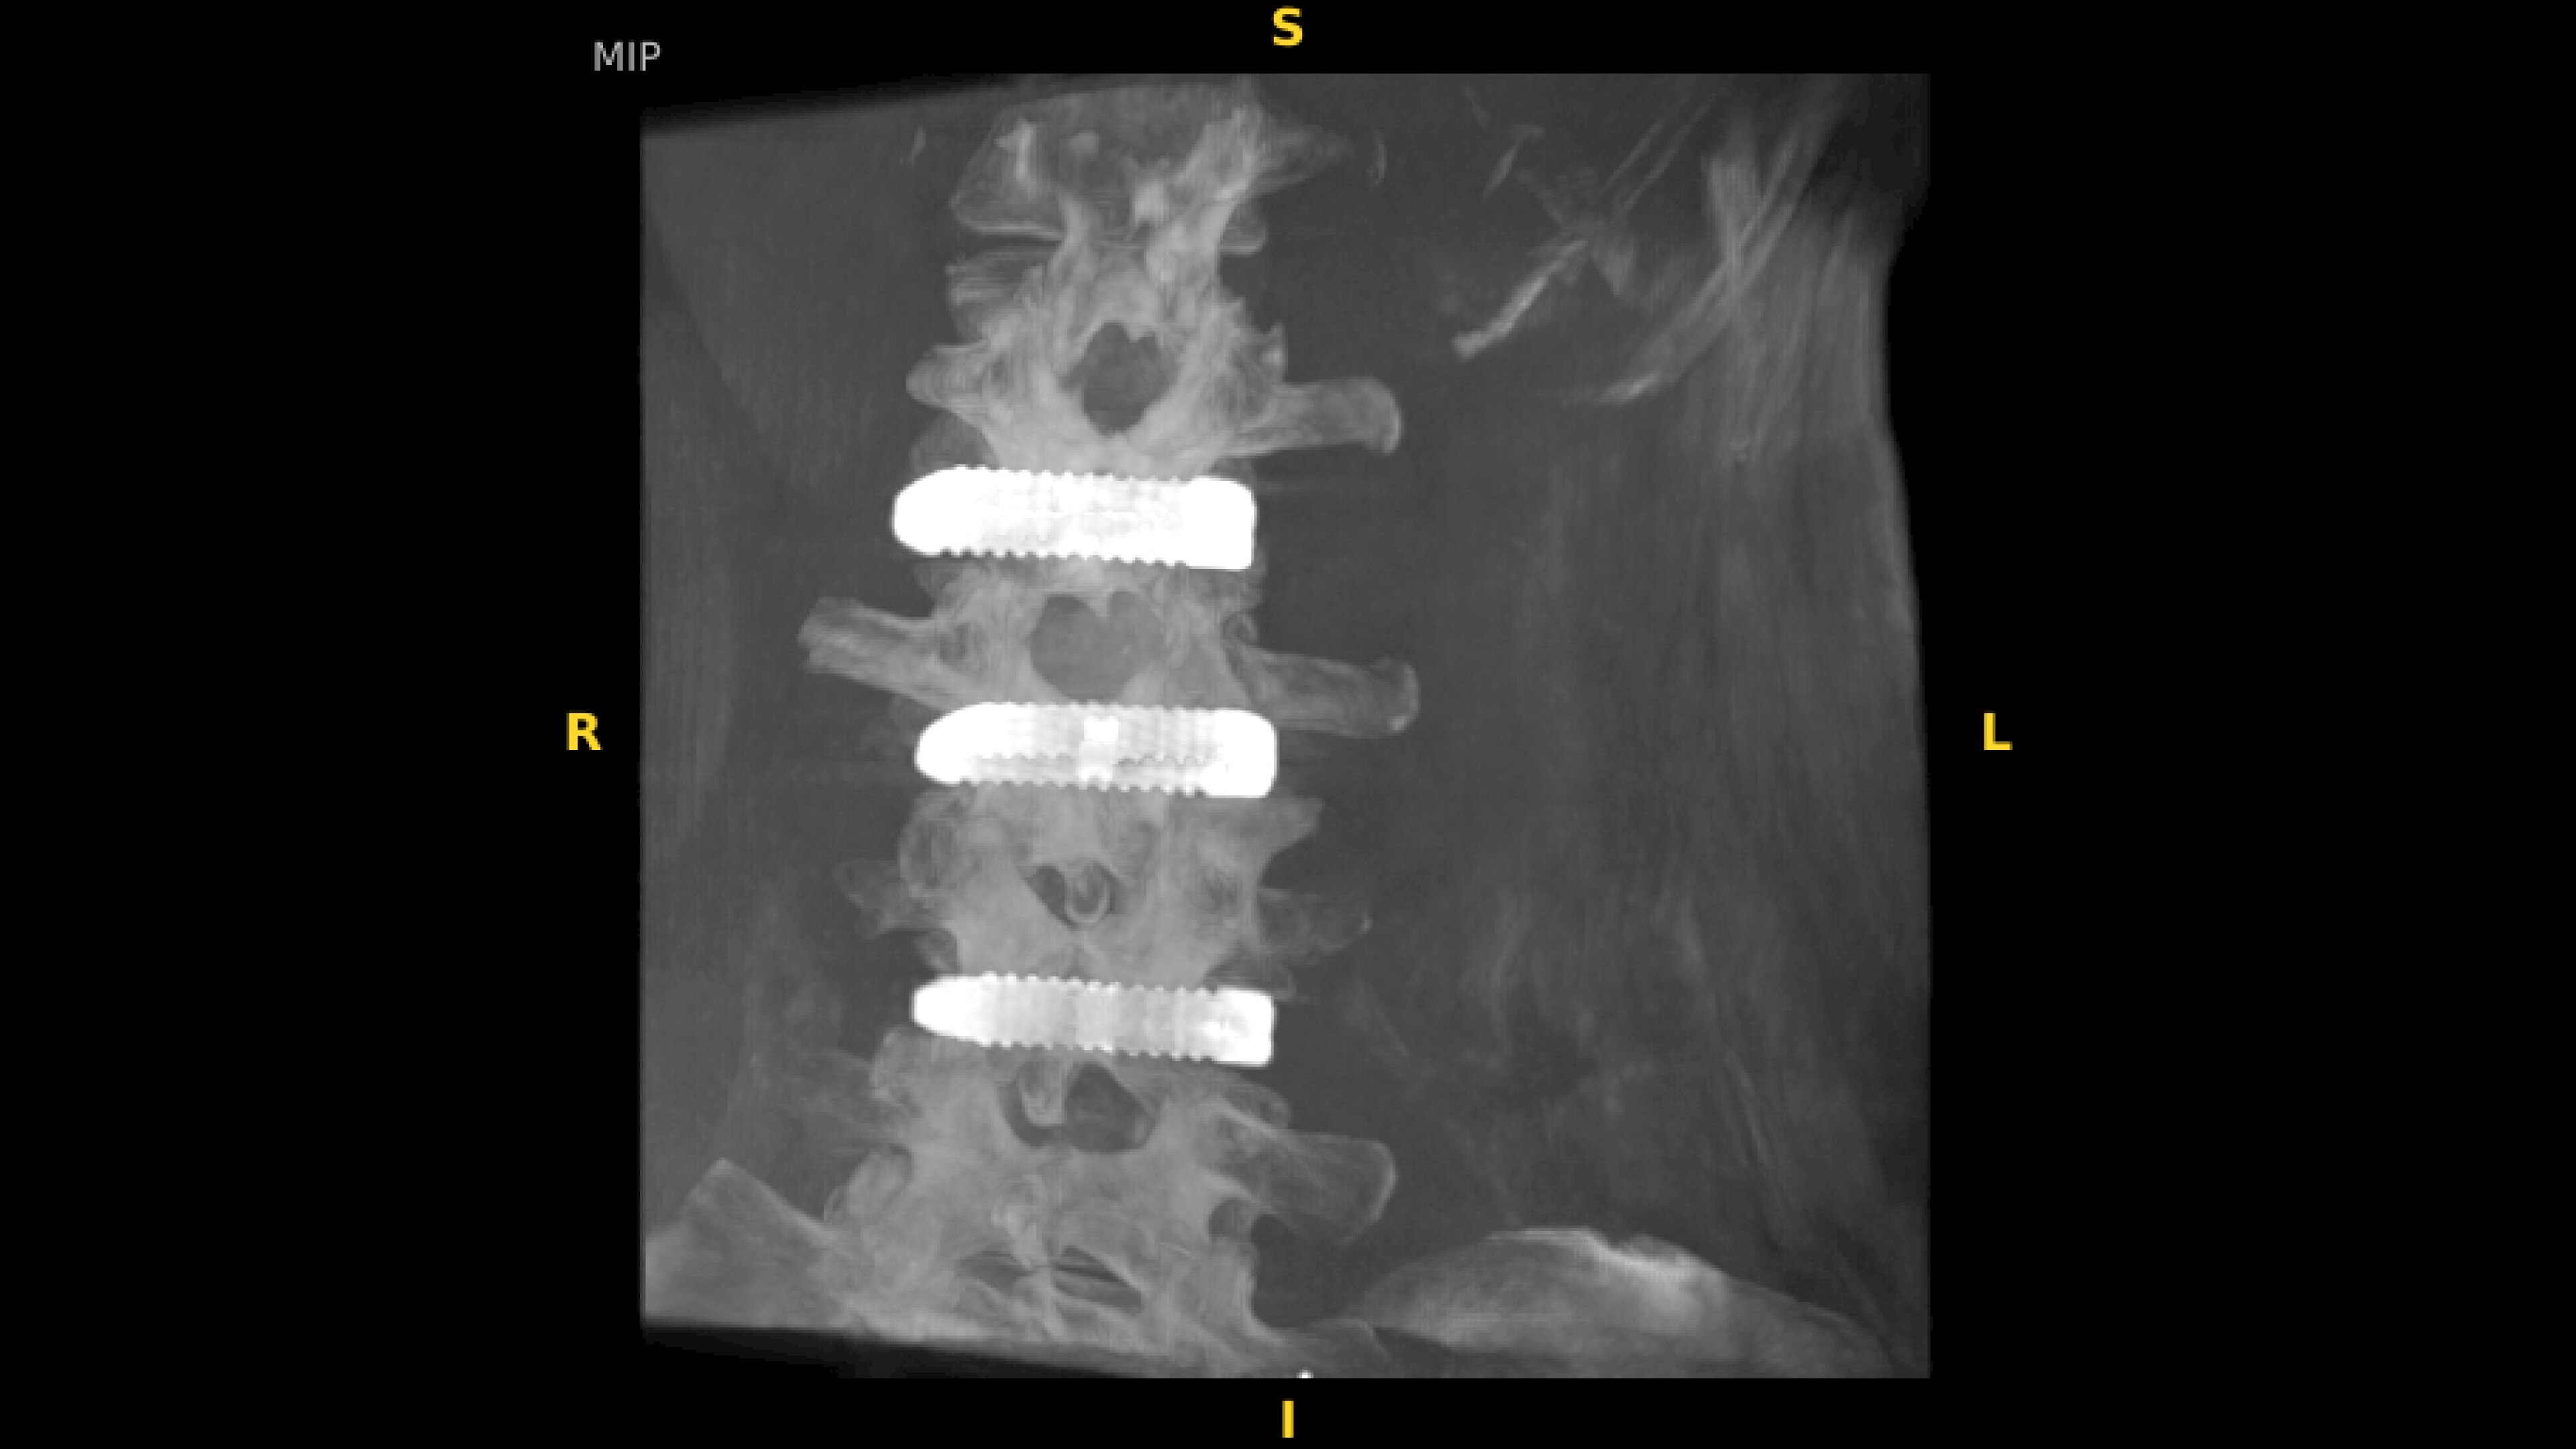

With OEC 3D, comprehensive imaging coverage of 19 cm x 19 cm x 19 cm 3D volumes and exceptional 2D images enables viewing several levels of the spine in the operating room.

The OEC 3D presents five perspectives: Axial, Coronal, Sagittal, MIP, and VR, on a 4K display for clear and detailed review of 3D volumes and 2D images